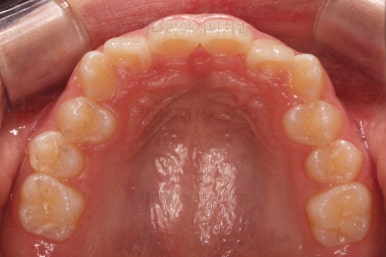

초진 시 입안의 모습입니다.

앞니가 안으로 굽어 들어간 양상인데요. 흔히 "옥니"라고 표현합니다.(뻐드렁니의 반대개념)

전반적으로 치열이 삐뚤삐뚤하고요.

우선 윗니에만 교정장치를 부착했습니다.

성장치료라더니 교정치료? 하실 수 있지만 윗니를 가지런하게 해준 이유는 아래턱을 앞으로 성장시켜줄려니 윗니 앞니가 옥니처럼 가로막고 있어서 아래턱이 앞으로 나올래야 나올 수 없는 상황이었어요.

그래서 앞니의 각도를 먼저 개선해주기로 했죠.

앞니의 각도가 앞으로 살아난 것이 보이실 거에요.

자연스레 과개교합 경향도 개선되어 어금니로 물렸을 때 아래 앞니가 점점 보이기 시작해요.